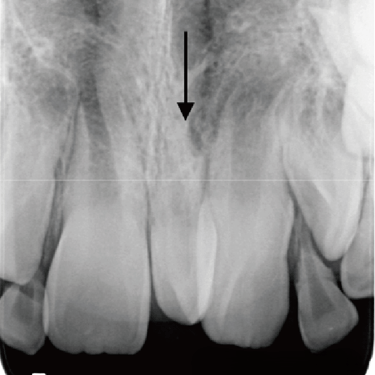

Quiste dentígero

Un quiste dentígero es un saco lleno de líquido que se forma alrededor de la corona de un diente no erupcionado.

Los pacientes pueden notar una hinchazón indolora en la mandíbula.

El tratamiento incluye la extirpación quirúrgica del quiste y, a veces, la extracción del diente involucrado.